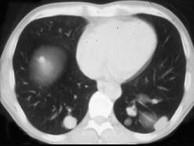

问题 女,38岁,低热乏力并消瘦2月余,CT如图所示,下列说法正确的是()

选项 A.左侧肾上腺区巨大的占位性病灶考虑为肾上腺癌 B.左侧肾上腺区巨大的占位性病灶考虑为嗜铬细胞瘤 C.左侧肾上腺区巨大的占位性病灶考虑为肾上腺腺瘤 D.肺内多发小结节病灶,考虑为肺转移瘤 E.肺内多发小结节病灶,考虑为肺结核

答案 AD